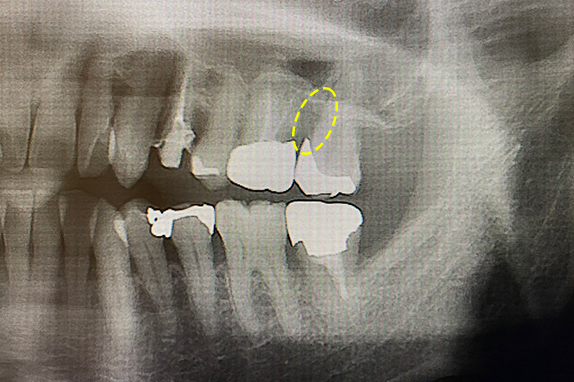

CASE 01 歯周再生治療

-

- 主訴

- 歯がグラグラで噛めない

-

- 回数期間

- 5回 約1年

-

- 治療法

- 歯周再生治療

-

- 治療費用

- 約17万円(税抜)

歯がグラグラで噛めないという主訴の患者様に歯周再生治療を用いて改善したケースです。レントゲン写真をみると術前は歯肉の退縮が見られるが、術後は歯肉の退縮が改善しています。

<リスク・副作用>

手術後は腫れ、痛み、痺れなどの副作用が生じる場合があります。